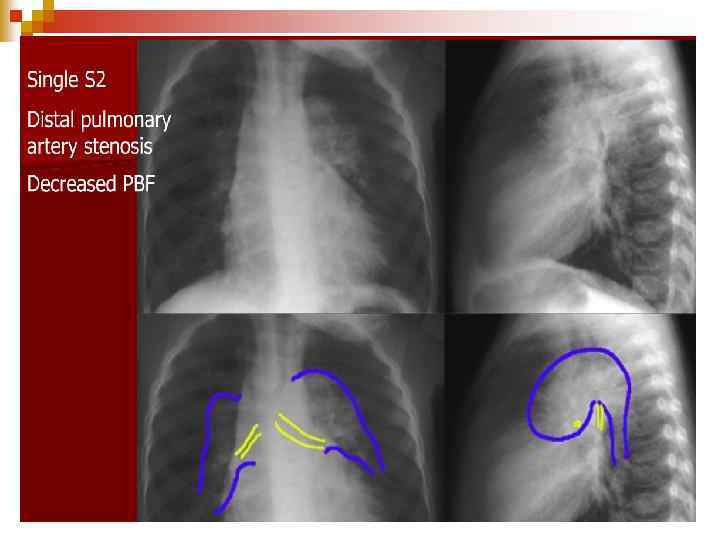

Pulmonary Hypertension/ Eisenmenger’s syndrome n PA radiograph demonstrates the heart is normal size with decreased pulmonary arterial markings, a prominent convex pulmonary artery and small aortic arch.

Ebstein’s anomaly n There is marked cardiomegaly with right atrial dilation and diminished pulmonary arterial markings.